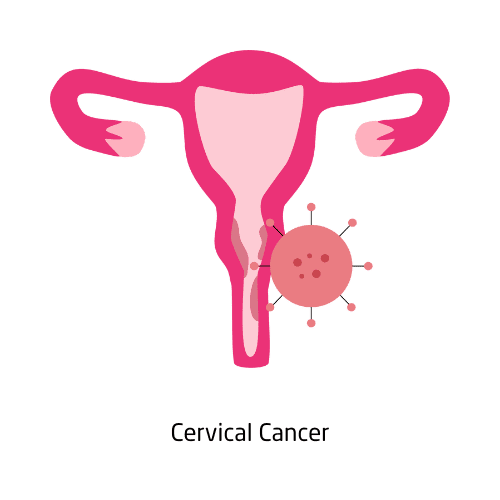

Cervical cancer starts in the cervix—the lower part of the uterus—and is primarily caused by long-term infection with high-risk strains of the human papillomavirus (HPV). Most cases can be prevented with the HPV vaccine and detected early through regular Pap smears and HPV testing. Symptoms may include abnormal bleeding, pelvic pain, or unusual discharge, but it often has no signs in early stages.

Treatment depends on the stage and may include surgery, radiation therapy, or chemotherapy. Education, screening, and vaccination are essential tools in preventing this disease. Global awareness campaigns continue to reduce cervical cancer rates.